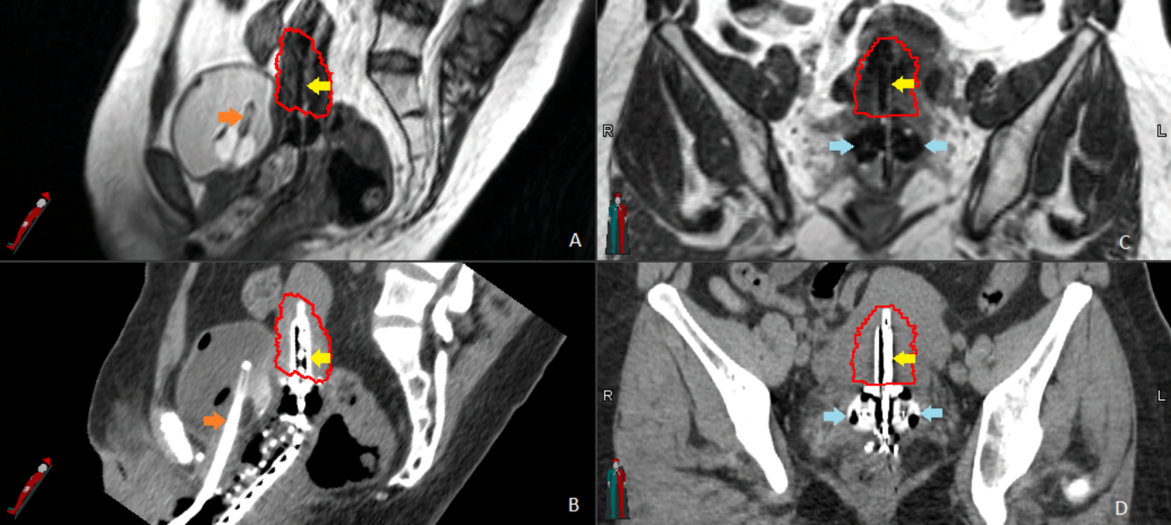

Image guided brachytherapy(IGBT) uses cross sectional image data to create 3D models.

IGBT is the use of advanced imaging technique to make brachytherapy more accurate and effective.

IGBT involves four phases:

- Placement of hollow catheters / carriers

- CT or MRI imaging

- Computer calculation of dose distribution called dosimetry

- Radiation treatment delivery